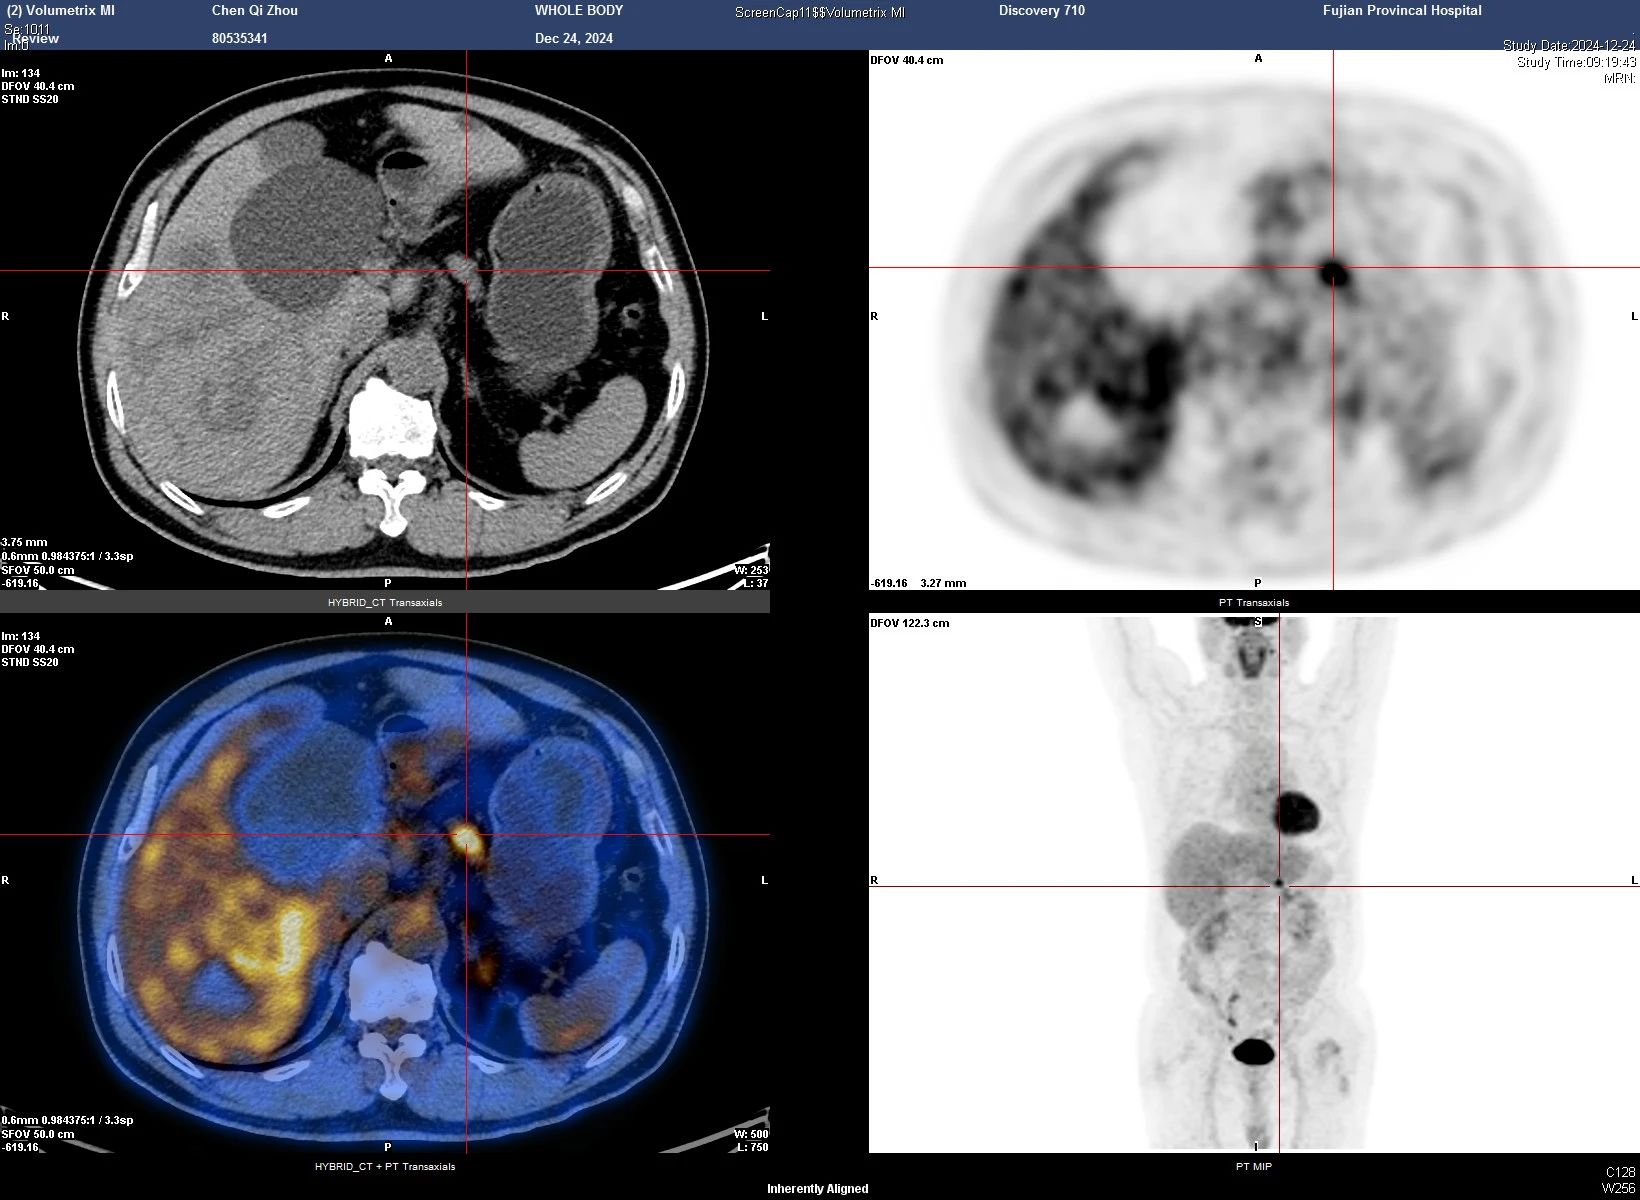

更让人揪心的是,陈老师还被检查出腹主动脉——右髂总动脉有一个范围达5.0×4.5cm的动脉瘤,并且动脉瘤周围已有破裂迹象

图示右髂总动脉瘤(黄色箭头)及可疑破裂处(红色箭头)

肝胆胰外科周松强主任医师介绍说,大动脉瘤体积越大,破裂风险越高,像陈老师这种囊状动脉瘤,破裂风险更为显著。一旦动脉瘤突发破裂,抢救成功率不超过10%。这三处隐患同时出现在陈老师身上,让他的病情变得异常复杂,每一处都足以致命,治疗难度可想而知。